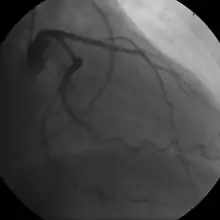

- Coronary angiography

Stable angina is the most common form of ischemic heart disease, and is associated with reduced quality of life and increased mortality. It is caused by epicardial coronary stenosis which results in reduced blood flow and oxygen supply to the myocardium.[72] Stable angina is characterized as short-term chest pain during physical exertion caused by an imbalance between myocardial oxygen supply and metabolic oxygen demand. Various forms of cardiac stress tests may be used to induce both symptoms and detect changes by way of electrocardiography (using an ECG), echocardiography (using ultrasound of the heart) or scintigraphy (using uptake of radionuclide by the heart muscle). If part of the heart seems to receive an insufficient blood supply, coronary angiography may be used to identify stenosis of the coronary arteries and suitability for angioplasty or bypass surgery.[73]